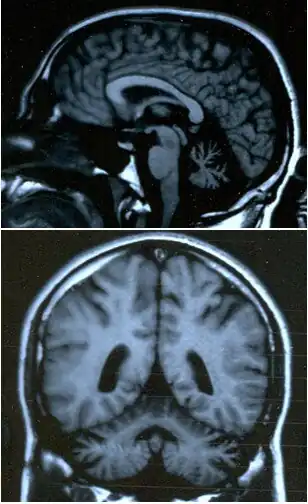

| Atrofia cerebelar, uma das possíveis causas. | |

É um sintoma característico de lesão cerebelar, mas também pode aparecer na ataxia de Friedreich, no meduloblastoma e na esclerose múltipla. Frequentemente aparece associada a dificuldade em articular algumas sílabas (disartria).[2]